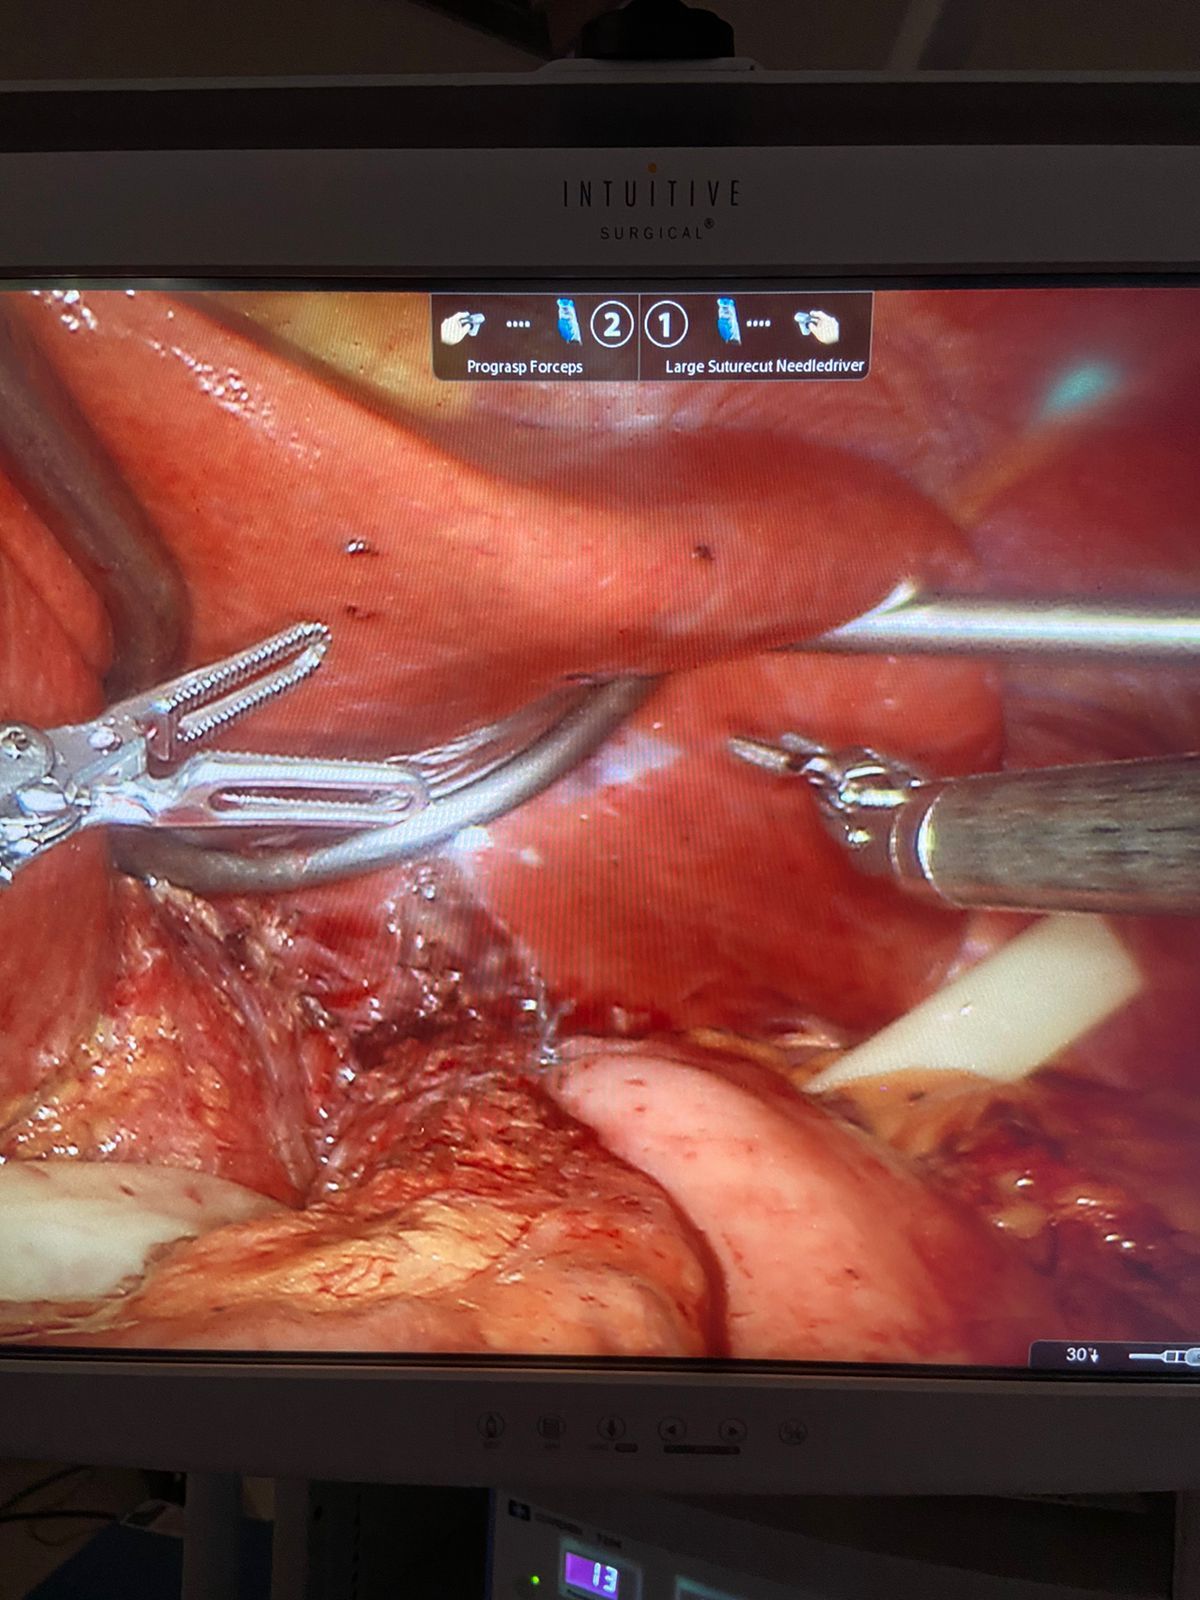

El sistema robótico cuenta con un brazo para la cámara y 3 brazos mecánicos, e instrumentos quirúrgicos montados en ellos. El cirujano controla los brazos mientras está sentado frente a una consola de computadora cerca de la mesa quirúrgica. La consola proporciona al cirujano una visión tridimensional aumentada de alta definición del sitio quirúrgico.